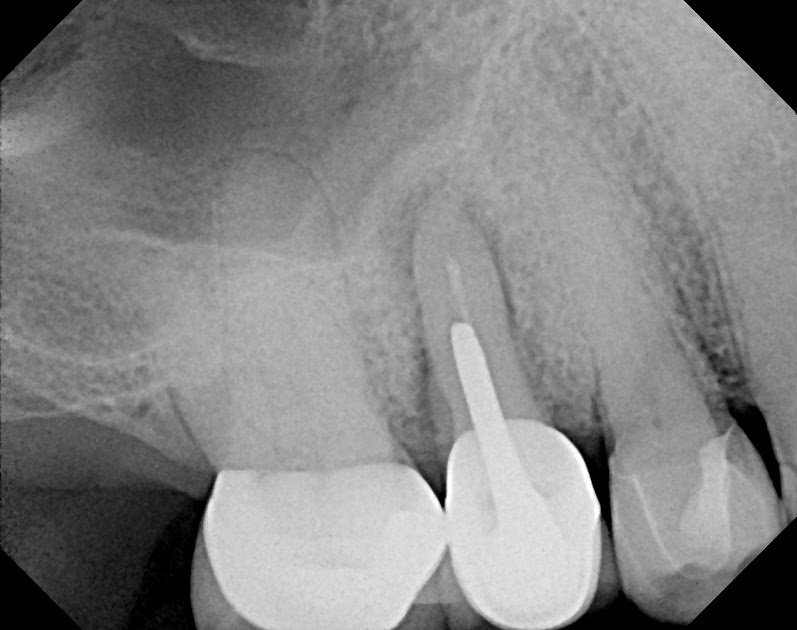

Radiographic view of root fracture of the maxillary left central Root Fracture X Ray There are some strong associations between radiographic findings and the presence of a root fracture. The current methods used to diagnose vrf are transillumination, radiographs, periodontal. Vrfs can be detected early by listening to the patient's chief complaints, carefully examining periapical and bitewing radiographs and performing a thorough clinical examination. Diagnosis of vrf is a difficult and challenging experience for. Root Fracture X Ray.

Root Fracture X Ray . The current methods used to diagnose vrf are transillumination, radiographs, periodontal. Diagnosis of vrf is a difficult and challenging experience for clinicians. Vrfs can be detected early by listening to the patient's chief complaints, carefully examining periapical and bitewing radiographs and performing a thorough clinical examination. Specifically, when the bone loss presents in a “j” shaped. There are some strong associations between radiographic findings and the presence of a root fracture. The accurate diagnosis of vrf may be challenging due to the absence of clinical signs, whilst. Dental fractures are often clinically apparent but can be overlooked in cases with associated facial fractures, especially as root. Vertical root fracture (vrf) is a common reason for the extraction of root filled teeth. The level of root fracture is important because it dictates the emergency and subsequent treatment.